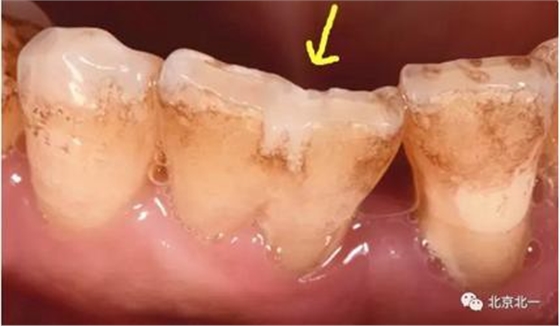

附:關(guān)注箭頭所示,診斷為結(jié)合牙還是融合牙?牙冠結(jié)合一起, 牙根分開(kāi)。